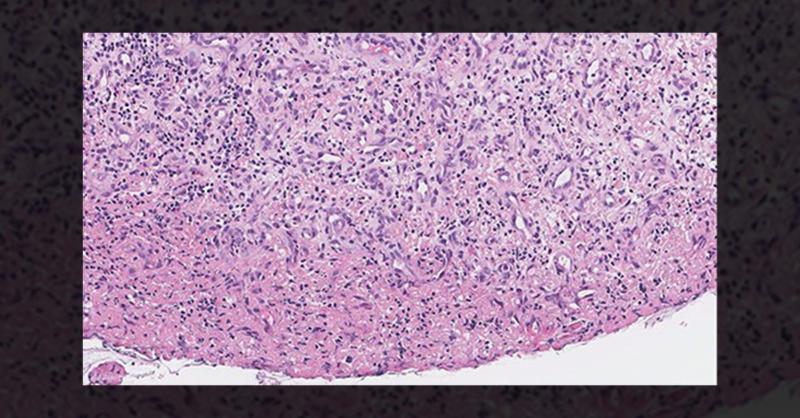

A 36-year-old male visited due to a gradually worsening hoarseness and dysphonia over the past three weeks. He denied experiencing any difficulty breathing, swallowing, shortness of breath, or weight loss. His medical and surgical history was unremarkable except for a history of using electronic cigarettes. Flexible laryngoscopic examination reveal